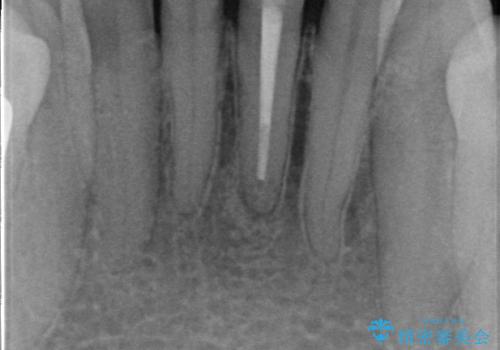

- 下顎前歯が茶色いのが気になるのでセラミックで治療したいといらっしゃった方の症例です。

再根管治療後、オールセラミッククラウン(スペシャル)による補綴を行いました。